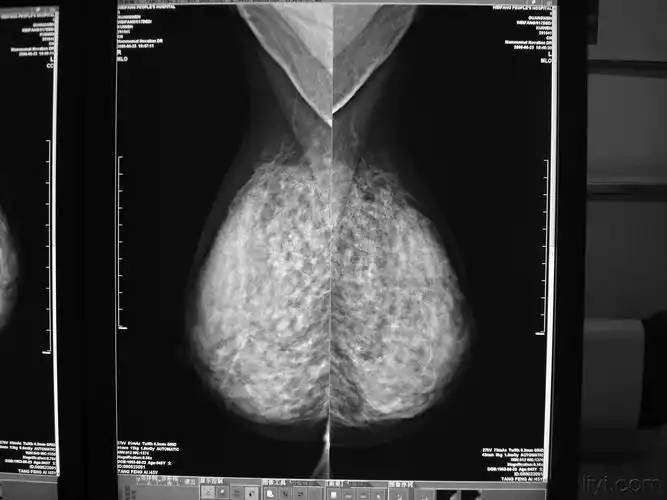

乳腺癌x,钼靶检查

乳腺钼靶检查